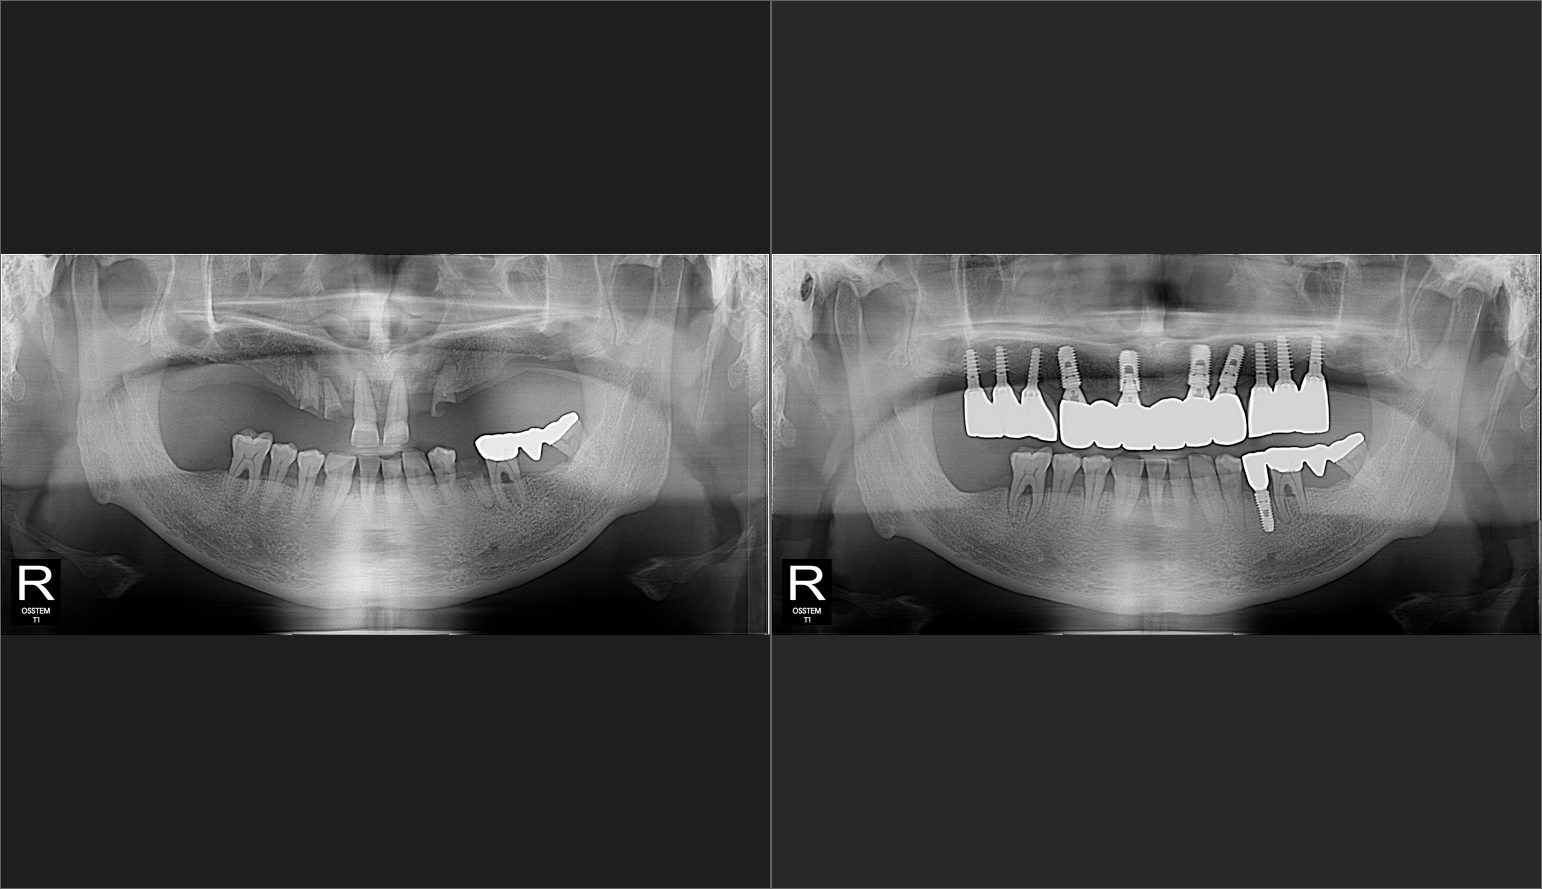

¼­¿ïÀÌ»ç¶ûÄ¡°úÀÇ ÃÖ÷´Ü 3D ½ºÄ³³Ê, 3D CT·Î ±âÁ¸ ¹æ»ç¼± »çÁø¿¡¼­ º¼ ¼ö ¾ø´ø ºÎºÐ±îÁö 3Â÷¿øÀûÀ¸·Î Á¤¹ÐÇÏ°Ô Áø´ÜÀÌ °¡´ÉÇÏ¿© ȯÀÚÀÇ °ñÁ¶Á÷, ÁÖº¯ Ä¡¾Æ¿ÍÀÇ °Å¸®, °¢µµ, ½Å°æÀ§Ä¡¸¦ È®ÀÎ ÇÒ ¼ö ÀÖ¾î Á¤È®ÇÑ ½Ã¼ú °èȹÀ» ¼¼¿ì°í Ä¡·áÀÇ ºÎÀÛ¿ëÀ» ÃÖ¼ÒÈ­ ÇÒ ¼ö ÀÖ½À´Ï´Ù.

Ä¡·áÈı⠻çÁø

Ä¡¾Æ±³Á¤ ÀüÈÄ »çÁø